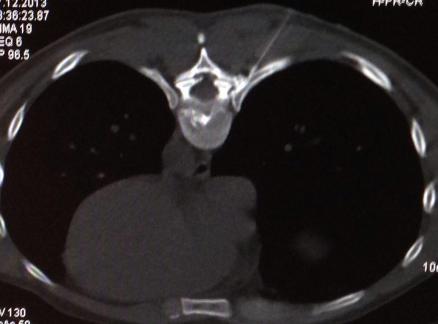

In lokaler Betäubung wird eine Laserfaser durch eine Punktionskanüle in die betroffene Bandscheibe eingeführt. Unter kontinuierlicher Röntgenkontrolle wird die Nadel millimetergenau platziert. Das Verfahren zählt zur Mikrotherapie und beruht auf der Schrumpfung von Bandscheibengewebe durch Hitze. Der innere Kern der Bandscheibe, der Nucleus pulposus, wird dabei schonend verkleinert. Ein Bandscheibenvorfall kann sich dadurch schneller zurückziehen. Es erfolgt eine rasche räumliche Entlastung der bedrängten Nervenwurzel. Weiterhin führt die Hitze zu einer Verödung der Schmerznerven, welche die Bandscheibe umgeben.

Der Eingriff dauert etwa 15 Minuten und wird in örtlicher Betäubung und leichter Sedierung durchgeführt.